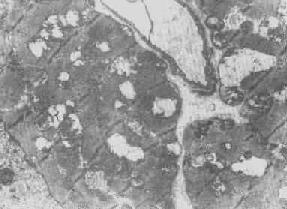

四、线粒体线粒体(mitochondrion)是细胞内主要的能量形成所在,故不论在生理上或病理上都具有十分重要的意义。 线粒体为线状、长杆状、卵圆形或圆形小体,外被双层界膜。外界膜平滑,内界膜则折成长短不等的嵴并附有基粒。内外界膜之间为线粒体的外室,与嵴内隙相连,内界膜内侧为内室(基质室)(图1-8)。在合成甾类激素的内分泌细胞(如肾上腺皮质细胞、卵甾滤泡细胞、睾丸的Leydig细胞等),线粒体嵴呈小管状。内外界膜的通透性不同,外界膜的通透性高,可容许多种物质通过,而内界膜则构成明显的通透屏障,使一些物质如蔗糖和NADH全然不能通过,而其他物质如Na+ 和Ca 2+等也只有借助于主动运输才能通过。线粒体的基质含有电子致密的无结构颗粒(基质颗粒),与二价阳离子如Ca2+及Mg2+具有高度亲和力。基质中进行着β氧化、氧化脱羧、枸橼酸循环以及尿素循环等过程。在线粒体的外界膜内含有单胺氧化酶以及糖和脂质代谢的各种转移酶;在内界膜上则为呼吸链和氧化磷酸化的酶类。 线粒体是对各种损伤最为敏感的细胞器之一。在细胞损伤时最常见的病理改变可概括为线粒体数量、大小和结构的改变: 1.数量的改变 线粒体的平均寿命约为10天。衰亡的线粒体可通过保留的线粒体直接分裂为二予以补充。在病理状态下,线粒体的增生实际上是对慢性非特异性细胞损伤的适应性反应或细胞功能升高的表现。例如心瓣膜病时的心肌线粒体、周围血液循环障碍伴间歇性跛行时的骨骼肌线粒体的呈增生现象。 线粒体数量减少则见于急性细胞损伤时线粒体崩解或自溶的情况下,持续约15分钟。慢性损伤时由于线粒体逐渐增生,故一般不见线粒体减少(甚至反而增多)。此外,线粒体的减少也是细胞未成熟和(或)去分化的表现。 2.大小改变 细胞损伤时最常见的改变为线粒体肿大。根据线粒体的受累部位可分为基质型肿胀和嵴型肿胀二种类型,而以前者为常见。基质型肿胀时线粒体变大变圆,基质变浅、嵴变短变少甚至消失(图1-9)。在极度肿胀时,线粒体可转化为小空泡状结构(图1-10,图1-11)。此型肿胀为细胞水肿的部分改变。光学显微镜下所谓的浊肿细胞中所见的细颗粒即肿大的线粒体。嵴型肿较少见,此时的肿胀局限于嵴内隙,使扁平的嵴变成烧瓶状乃至空泡状,而基质则更显得致密。嵴型肿胀一般为可复性,但当膜的损伤加重时,可经过混合型而过渡为基质型。 线粒体为对损伤极为敏感的细胞器,其肿胀可由多种损伤因子引起,其中最常见的为缺氧;此外,微生物毒素、各种毒物、射线以及渗透压改变等亦可引起。但轻度肿大有时可能为其功能升高的表现,较明显的肿胀则恒为细胞受损的表现。但只要损伤不过重、损伤因子的作用不过长,肿胀仍可恢复。 线粒体的增大有时是器官功能负荷增加引起的适应性肥大,此时线粒体的数量也常增多,例如见于器官肥大时。反之,器官萎缩时,线粒体则缩小、变少。

图1-8 心肌细胞线粒体

图1-9 线粒体肿